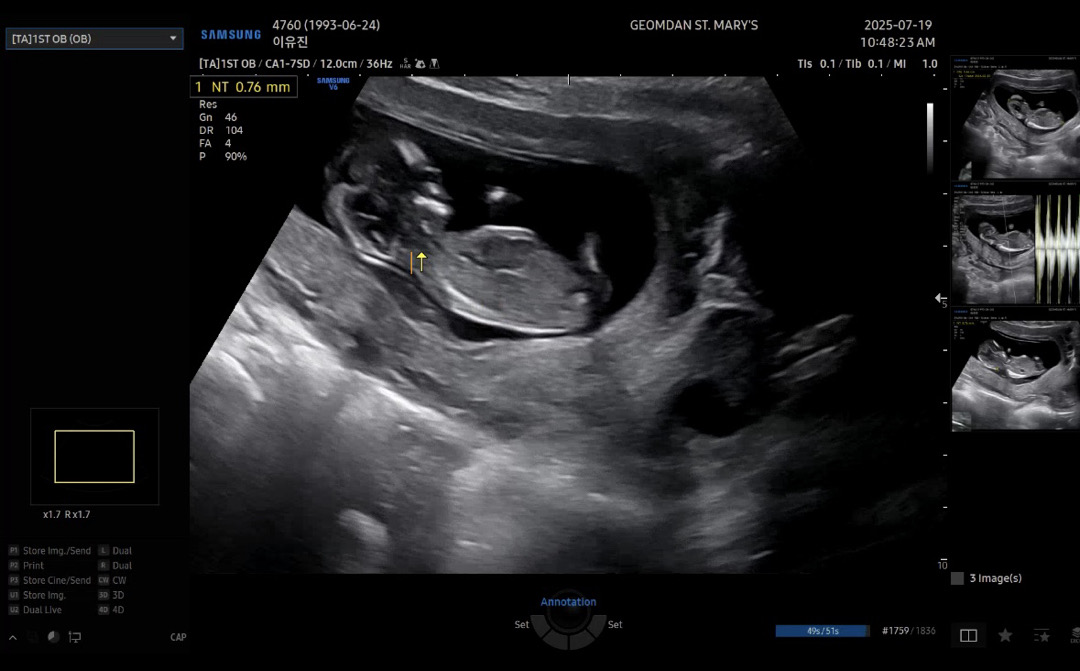

12์ฃผ์ฐจ ์ฉ์ฉ์ด์์๐ด ํผ์ ๊ณต๋ถํ ๊ฐ๋๋ฒ์ ๋ธ์ธ๋ฐ ํ์ ์ด ์๋ค์ใ ใ ๋์ฌ๋๋ค ๋์์ฃผ์ธ์~๐ค